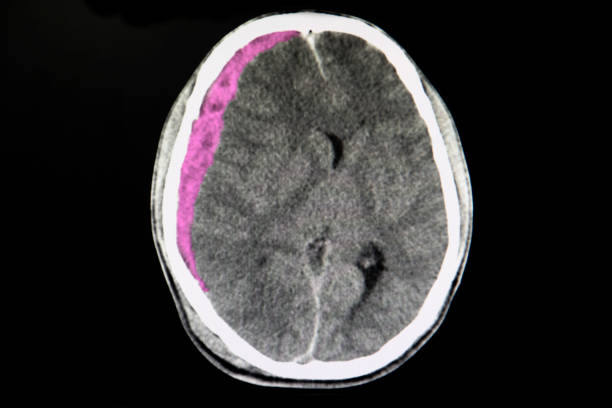

뇌출혈은 뇌안에 있는 혈관에서 출혈이 발생하여 뇌조직이 손상을 입는 질환이며, 중증의 뇌혈관질환 중 하나입니다. 일반적으로 고혈압, 동맥류, 혈관 기형, 혈전 등의 이유로 혈관이 파열하거나 뚫리면서 발생합니다.

고혈압은 뇌출혈을 일으키는 가장 일반적인 원인 중 하나입니다. 고혈압은 혈관벽을 약화시켜 혈관이 파열하기 쉽게 만들기 때문입니다. 또한, 혈관에 생긴 약간의 이상증상이나 동맥류, 혈관 기형 등도 뇌출혈의 원인이 될 수 있습니다.